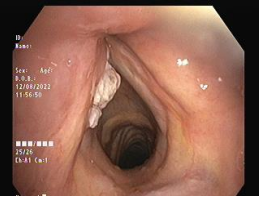

Figures 1,2,3,4

Figure 2